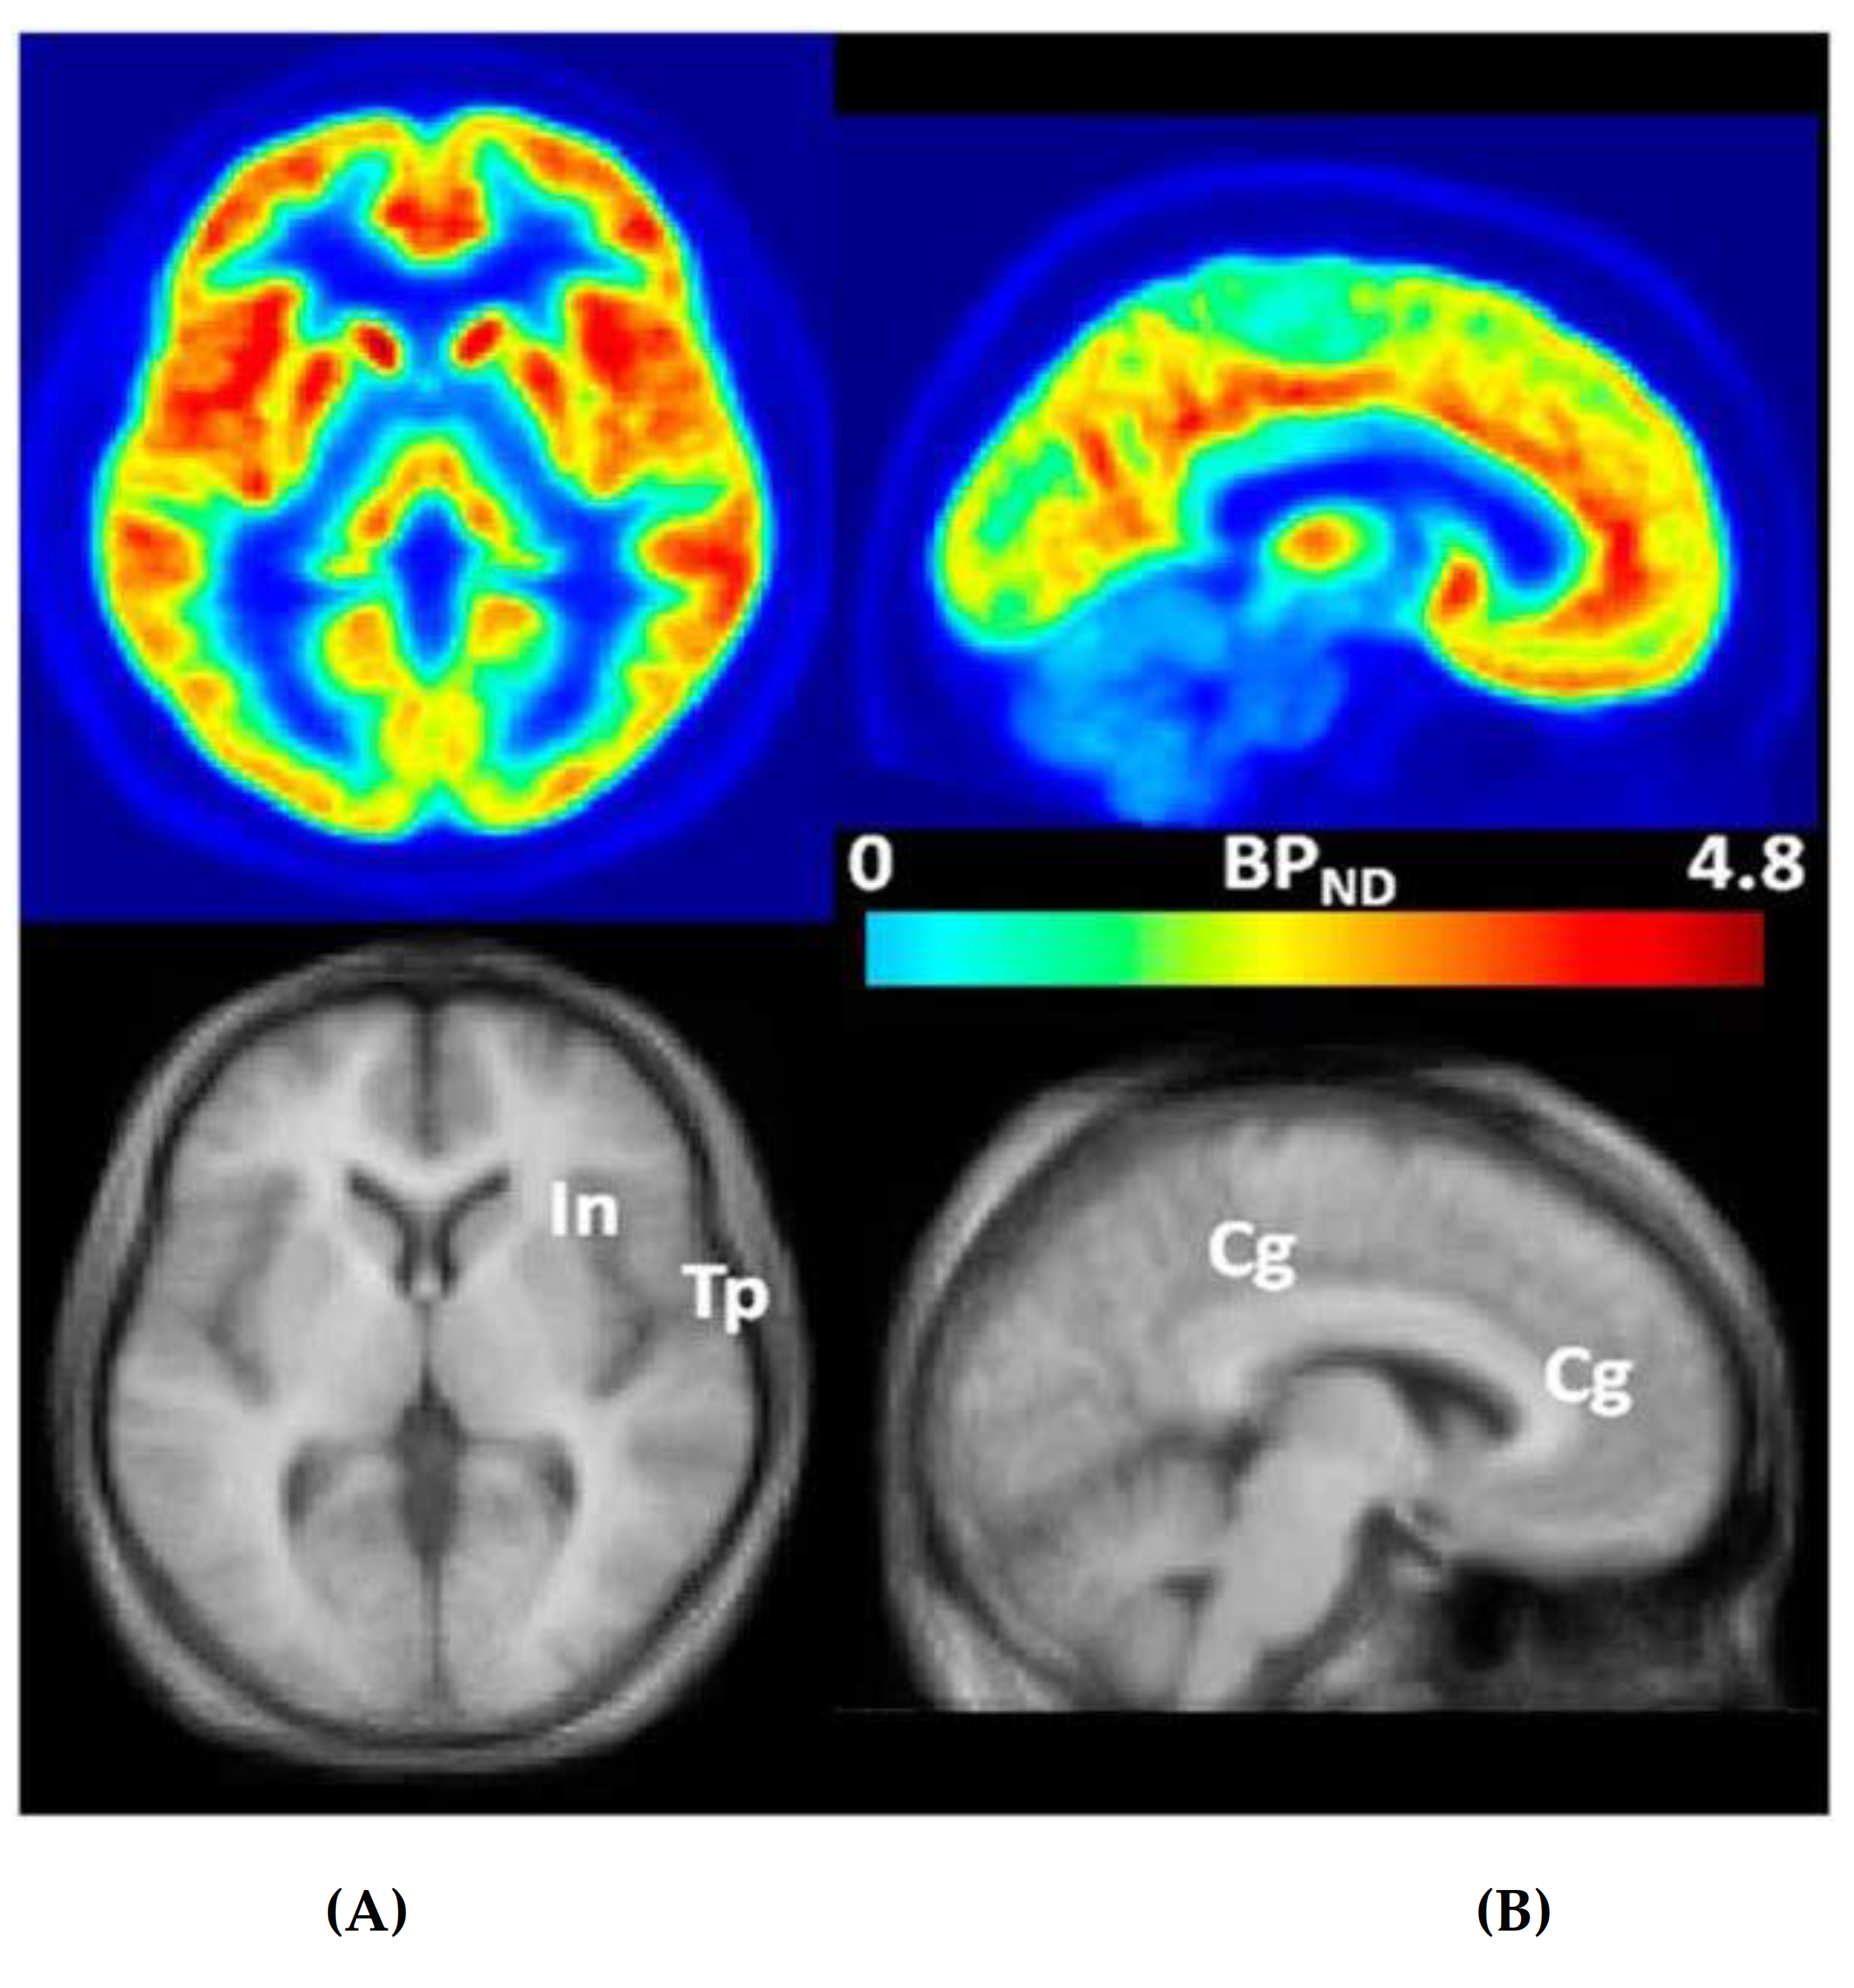

4.2.1. Positron Emission Tomography (PET)